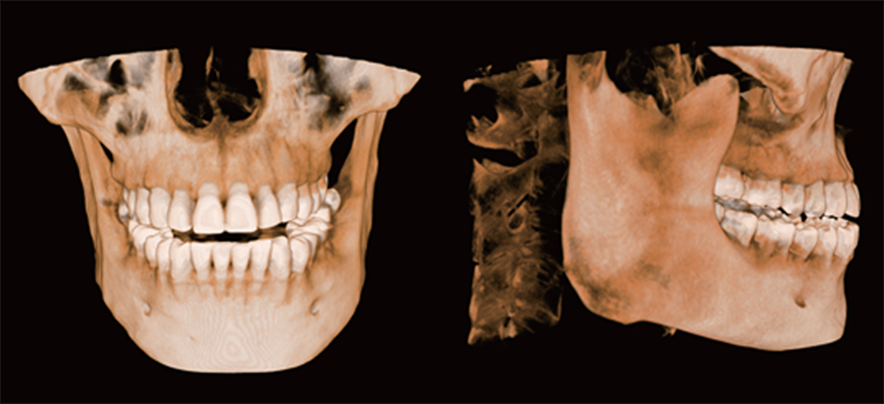

The LargeV CBCT supports CT, CEPH, and panoramic imaging in one compact system.

It delivers sharp, high-contrast images that reveal every dental structure with exceptional clarity.

High-Resolution Dental CBCT Imaging

The system achieves image resolutions up to 2.0 lp/mm with a voxel size range of 0.05 – 0.25 mm.

Furthermore, the high-definition image output ensures accurate diagnosis and confident treatment planning.

Furthermore, Panoramic Images are Reconstructed from 3D Dental CBCT data for clearer visualization

Furthermore, AI+PAN Dental CBCT Imaging enhances precision.

- The system rebuilds panoramic views directly from CBCT data using AI.

- Panoramic auto-focus and multi-layer technology select the best curve automatically.

- Therefore, the final image is cleaner and easier to read.